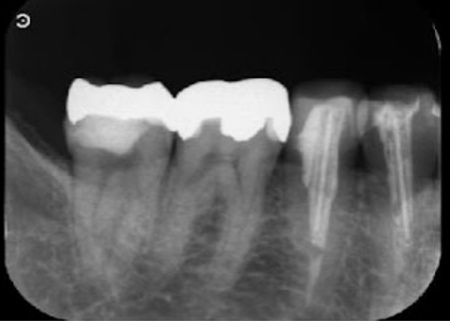

拝見したところ、右下奥歯(第2小臼歯)の歯根の先に、細菌感染による炎症「根尖(こんせん)病巣」が認められました。

詳しく検査をした結果、感染により歯根の先の骨が溶けていることもわかりました。

また、右下奥歯2本(第1大臼歯、第2大臼歯)には歯科用の白いプラスチック素材「コンポジットレジン」が詰められていましたが、歯ぎしりによって削れ、その下で虫歯が進行しています。

このまま放置すると、炎症がさらに広がって周囲の歯や骨に悪影響が及んだり、虫歯がさらに進行したりするおそれがあるため、早急に治療をする必要があると診断しました。